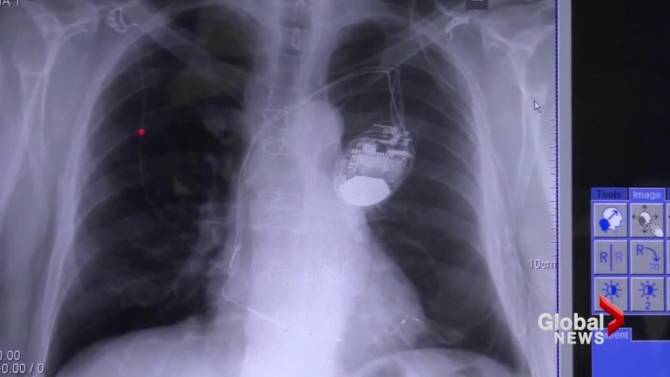

The mother of three suffers from a rare cardiac condition and needs a pacemaker/defibrillator to manage it. One of the leads — the long wires that attach the device to the heart muscle — had fractured and was shocking her repeatedly with 80 joules of energy.

St. Paul’s Hospital has become a world leader in the retrieval and insertion of new leads. Robinson’s third trip to the OR was actually the hospital’s 1,000th procedure. The surgeons use what is known as an excimer laser to cut away scar tissue and free up the wire that is pulled out from a small incision in the patient’s chest. The laser is expensive ($250,000 was provided by the St. Paul’s Hospital Foundation).

Robinson had a new type of device implanted in her chest, one that doesn’t actually touch her heart. A wire is placed just under the skin and monitors her heart remotely. It’s much more robust, much less invasive, and much easier to fix if there is a problem.